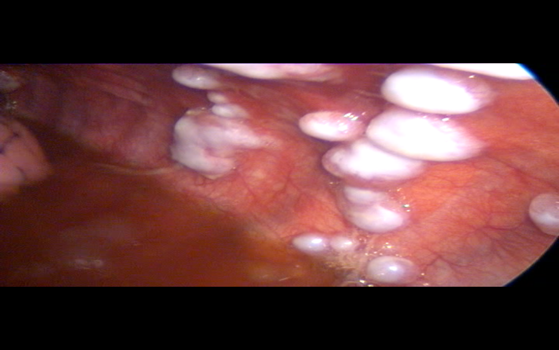

Under short GA, Diagnostic Thoracoscopy was done through left 5th ICS Mid axillary Line. Large white colored multiple pleural nodules were found deposited on the parietal pleura.

Fig 1

Final Diagnosis – Metastatic AdenoCarcinoma

Figure 1